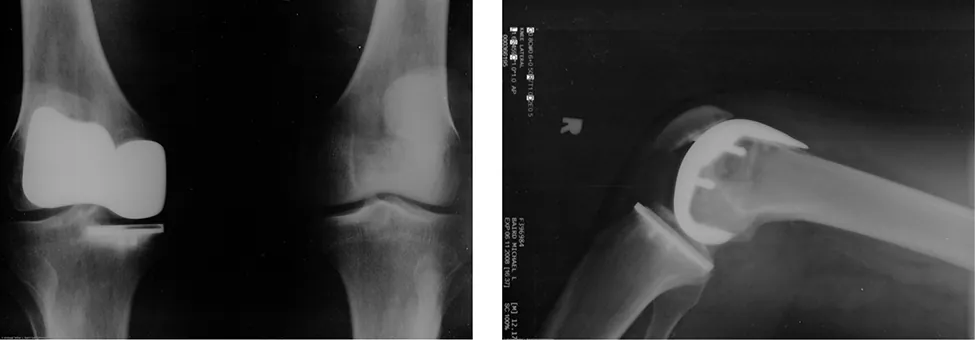

Wielu ludzi doświadczyło, jak ślisko jest, gdy chodzi się po lodzie. Tymczasem wiele części ciała, zwłaszcza stawów, ma znacznie mniejsze współczynniki tarcia – często trzy lub cztery razy mniejsze niż lód. Staw to miejsce styku dwóch kości, zwykle pokryte grubą warstwą tkanki łącznej (chrząstki). Staw kolanowy tworzą dalszy koniec kości udowej i bliższy koniec kości piszczelowej. Biodro jest stawem kulistym (na końcu kości udowej) i panewkowym (część miednicy). Końce kości w stawie są przykryte chrząstkami, co zapewnia gładką, niemal szklaną powierzchnię. Stawy wytwarzają też płyn (maź stawowa), który redukuje tarcie i zużycie. Zużyty lub uszkodzony staw może zostać wymieniony sztuczny staw (Ilustracja 6.12). Elementy zamienne mogą zostać wykonane z metalu, ceramiki lub plastików (polietylen) o bardzo niskim współczynniku tarcia.

Zdjęcie rentgenowskie sztucznego kolana.

Ilustracja 6.12 Wstawianie sztucznego stawu kolanowego jest procedurą stosowaną od ponad 20 lat. Na rysunku przedstawiono zdjęcia rentgenowskie sztucznego stawu kolanowego. (Żródło: Mike Baird)